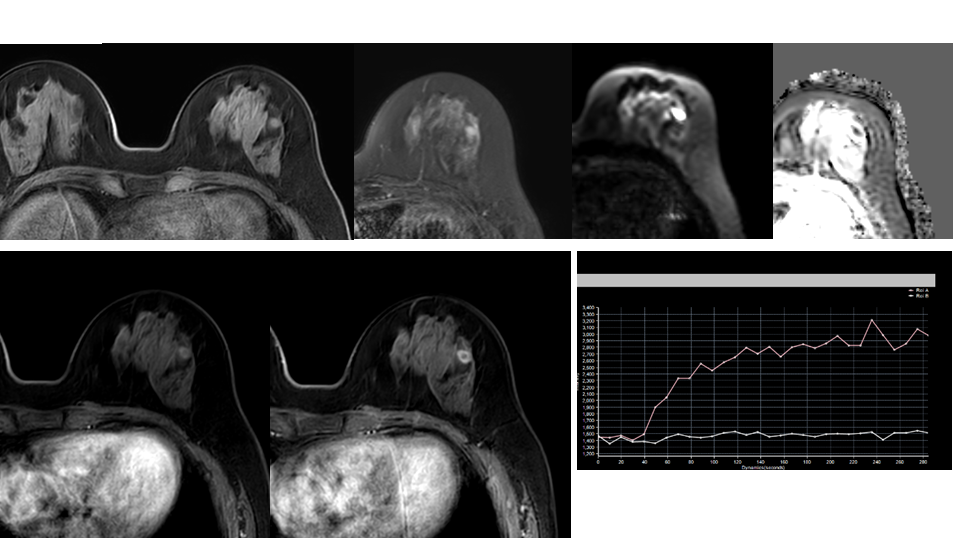

【病例】纤维囊性乳腺病伴纤维腺瘤形成 VS 乳腺增生病并间质硬化-5

【病例】纤维囊性乳腺病伴纤维腺瘤形成 VS 乳腺增生病并间质硬化-6